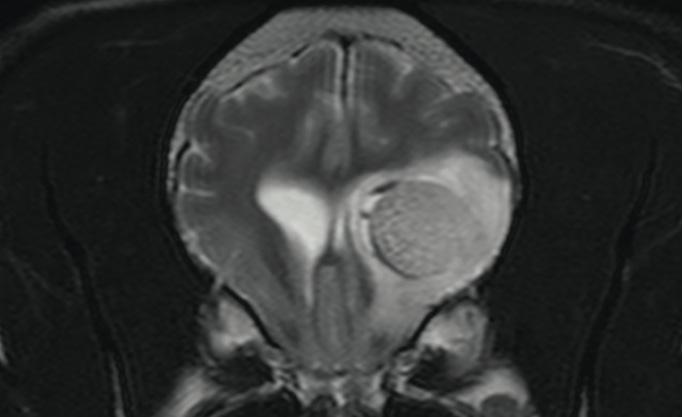

Follow-up of a patient with a glioma in the posterior part of the olfactory brain (lobus piriformis) after radiation therapy. In the picture at the top before treatment and in the picture at the bottom six months after radiation therapy; a strong reduction of the tumor size and the surrounding swelling can be seen.